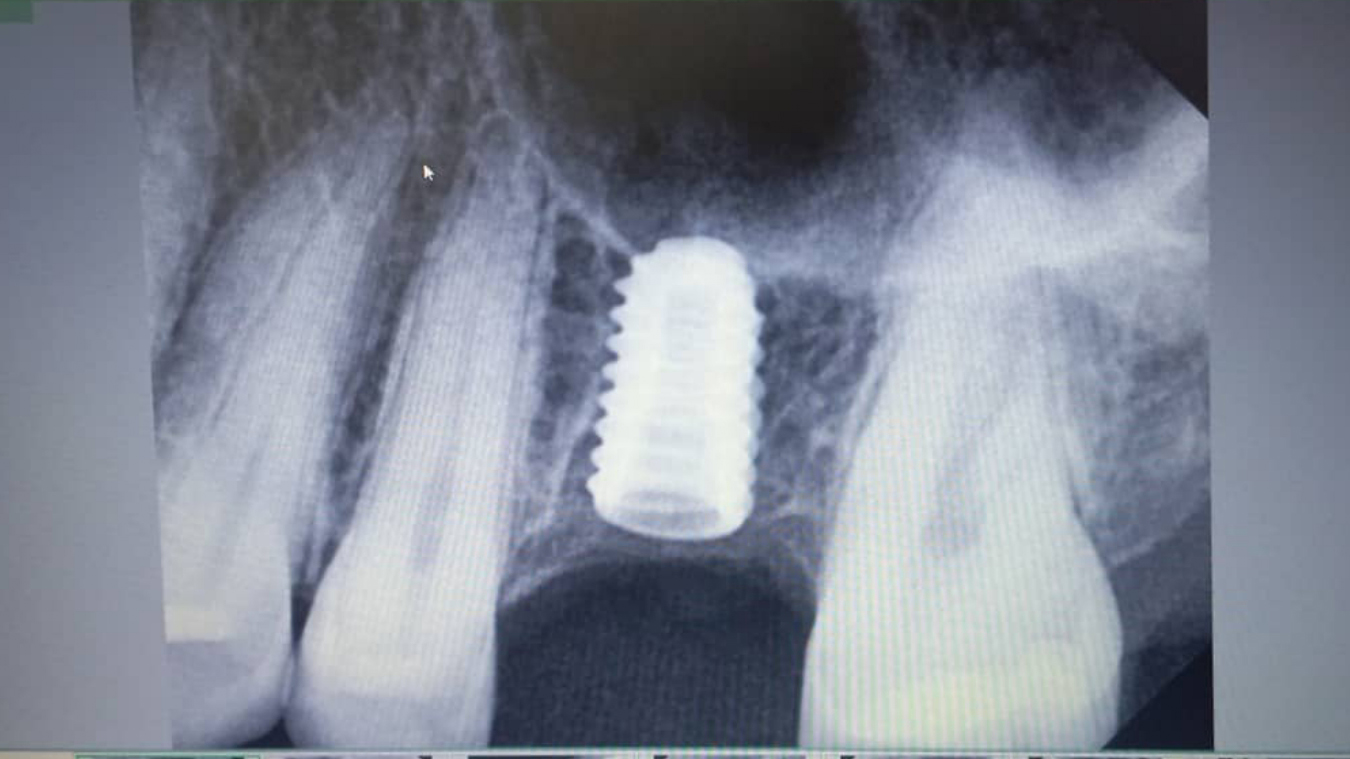

Dental implants are titanium posts surgically placed into the jawbone to serve as artificial tooth roots. This procedure provides a strong foundation for replacement teeth, ensuring stability and durability. Our skilled oral surgeons conduct thorough assessments to determine the suitability of implants for each patient, taking into consideration bone density, oral health, and individual needs.

The implant process typically involves several stages, starting with the surgical placement of the implant, followed by a healing period during which the implant fuses with the bone—a process known as osseointegration. After sufficient healing, custom-made crowns are affixed to the implants, restoring both function and natural appearance. This approach allows patients to enjoy improved chewing ability and confidence in their smiles.